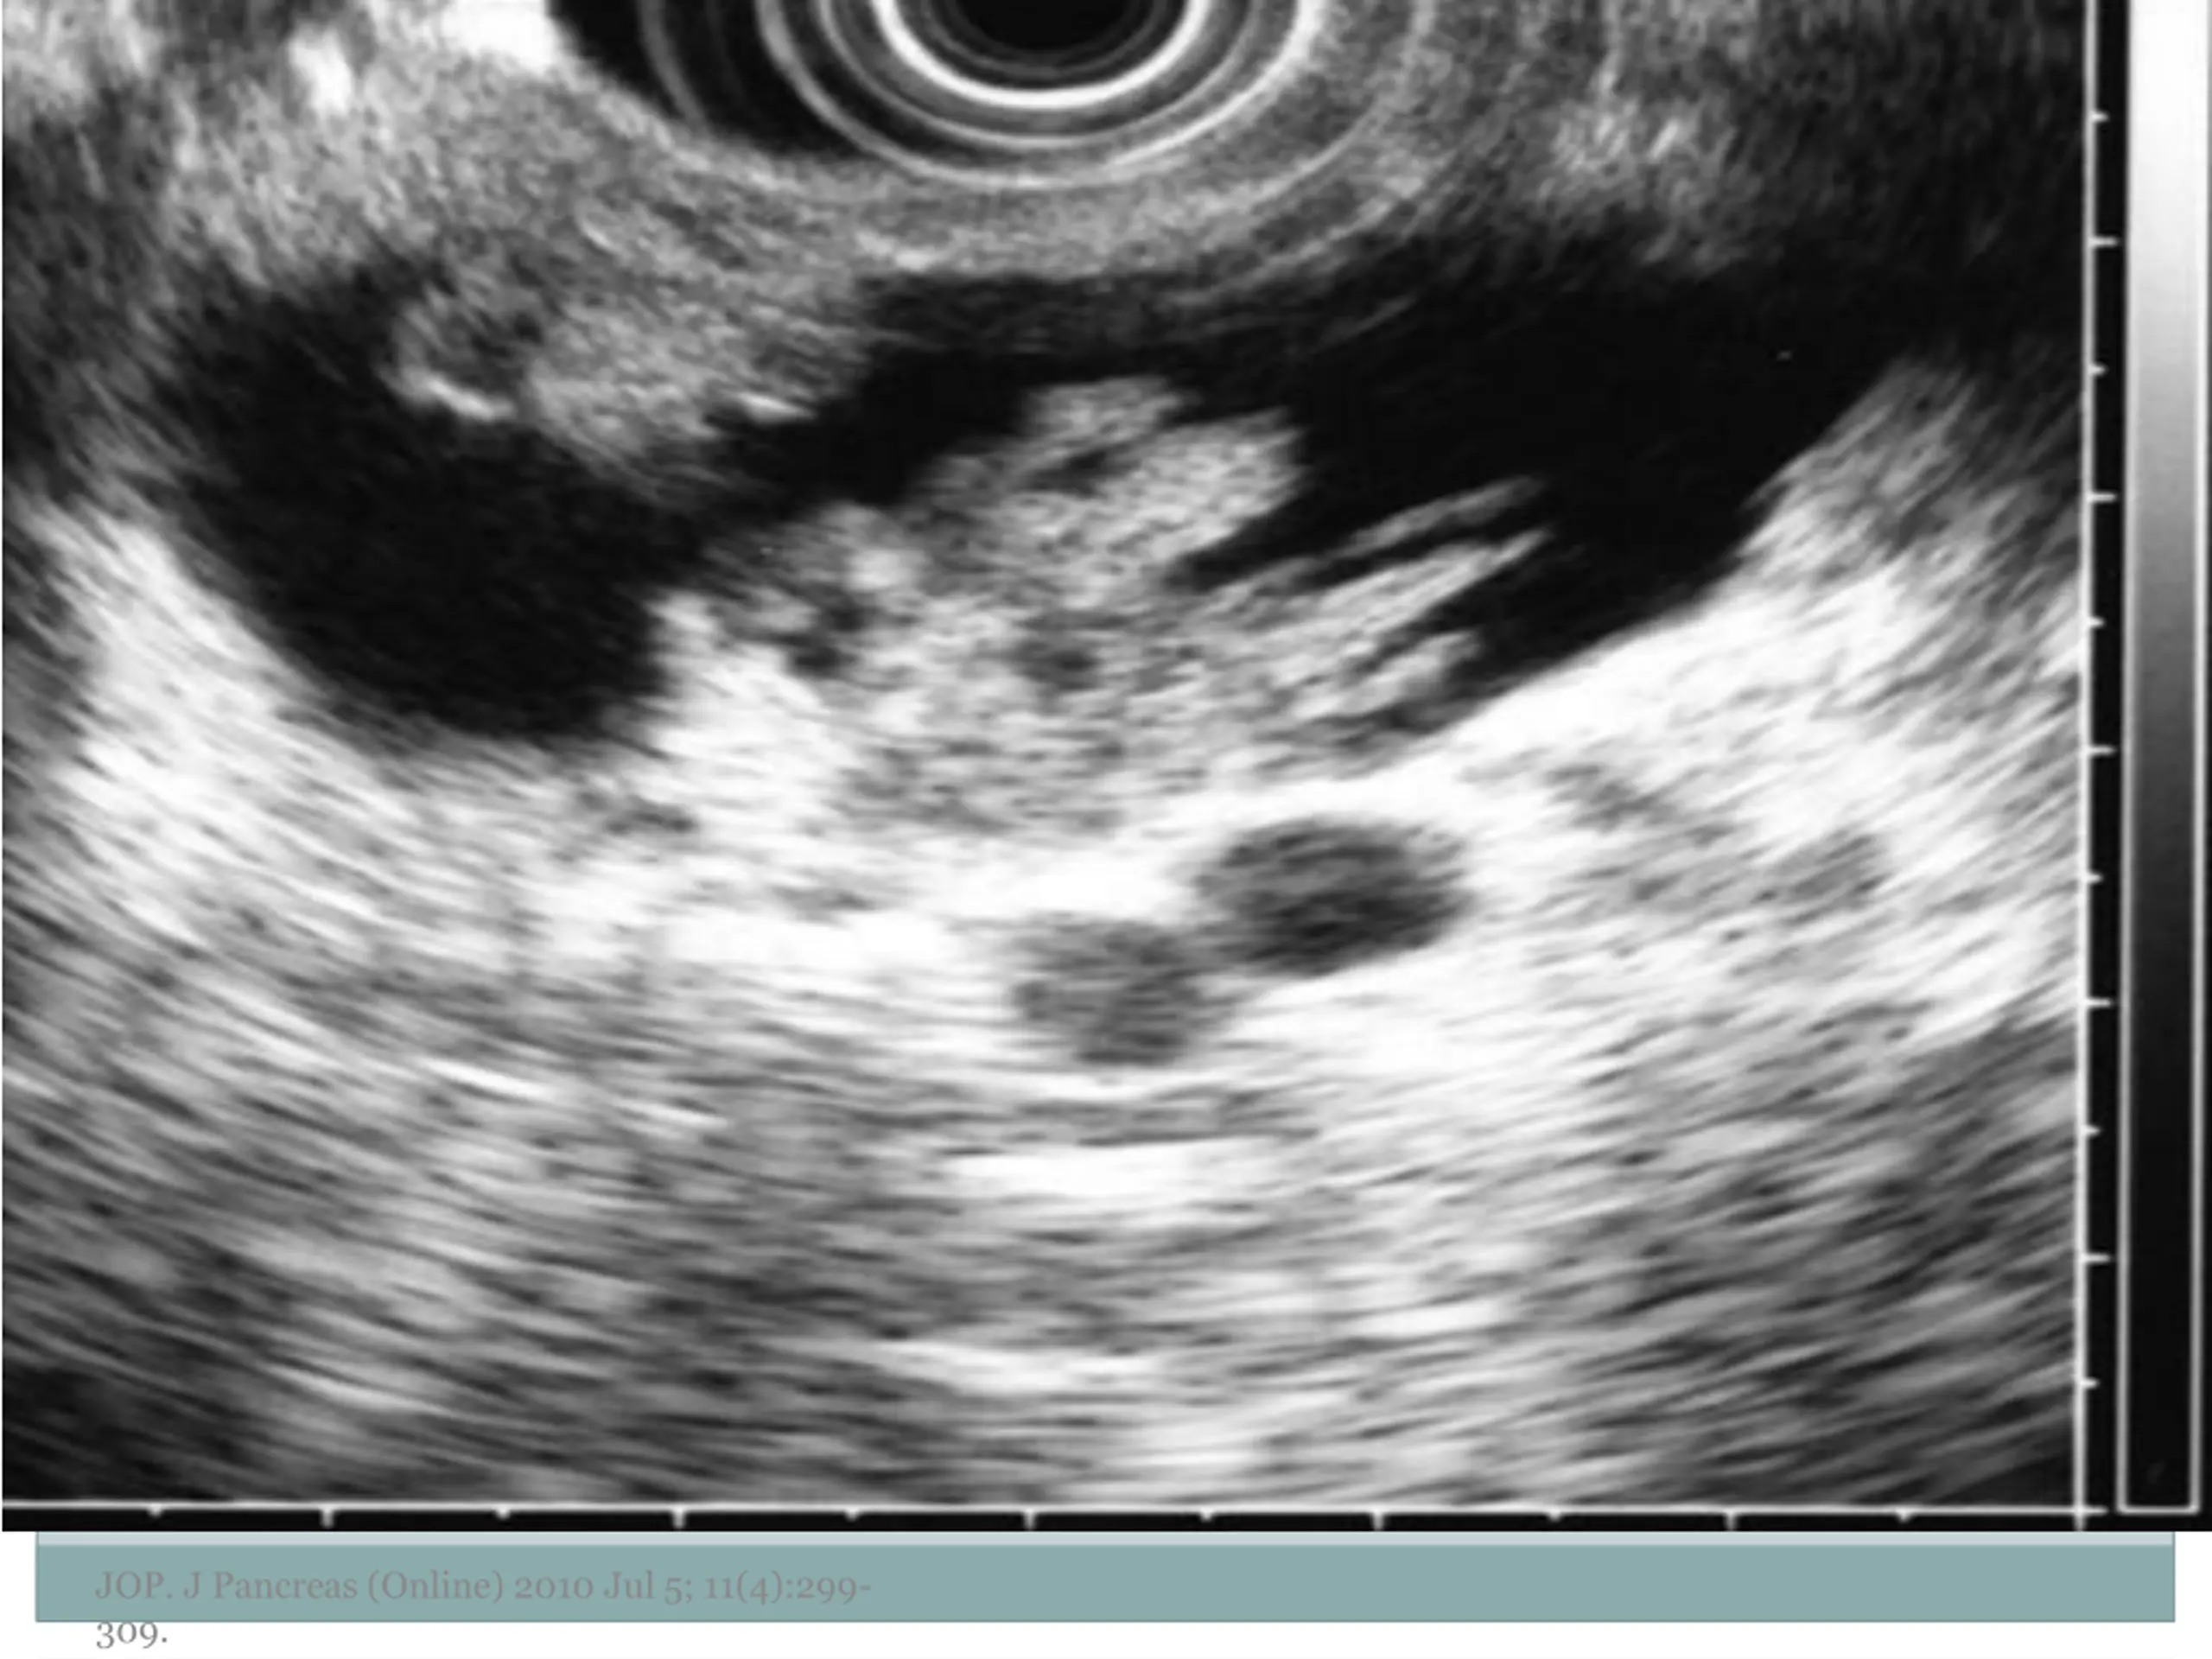

7. EUS Morphology Cyst wall Thick vs. thin Solid component Associated with malignancy Septations Micro vs. macrocystic Ductal abnormalities Main duct vs. side duct Number of cyst Lymphadenopathy EUS morphology can correctly differentiate mucinous from non-mucinous cystic lesions approximately 50% of the time JOP. J Pancreas (Online) 2010 Jul 5; 11(4):299- 309.

10. Examples of Morphology JOP. J Pancreas (Online) 2010 Jul 5; 11(4):299- 309.

11. JOP. J Pancreas (Online) 2010 Jul 5; 11(4):299- 309.